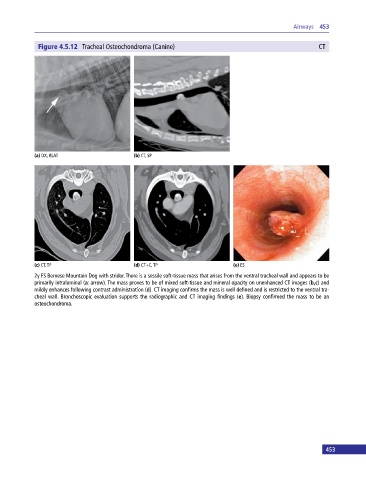

Figure 4.5.12 Tracheal Osteochondroma (Canine) CT

2y FS Bernese Mountain Dog with stridor. There is a sessile soft‐tissue mass that arises from the ventral tracheal wall and appears to be

primarily intraluminal (a: arrow). The mass proves to be of mixed soft‐tissue and mineral opacity on unenhanced CT images (b,c) and

mildly enhances following contrast administration (d). CT imaging confirms the mass is well defined and is restricted to the ventral tra

cheal wall. Bronchoscopic evaluation supports the radiographic and CT imaging findings (e). Biopsy confirmed the mass to be an

osteochondroma.